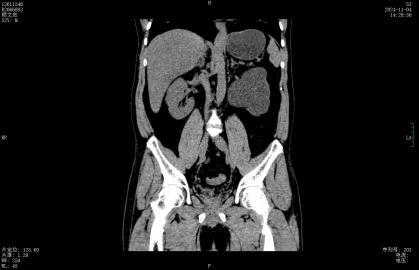

今年8月起,左腰部酸胀频繁不适,这才想起医生曾经的叮嘱,后找到深圳市罗湖区人民泌尿外科姜刚刚副主任医生门诊就诊,行CT检查发现整个左肾重度积水,而结石仍旧卡在输尿管内,最终只能无奈手术切除没有功能的左肾。

肾积水就像水管堵塞会导致水池溢水一样,结石堵塞了尿路,尿液排不出去就会回流,导致肾脏被越撑越大,这就是“肾积水”。长期的积水会像泡在水里一样,压迫并损坏肾脏的实质细胞,导致肾功能永久性丧失。